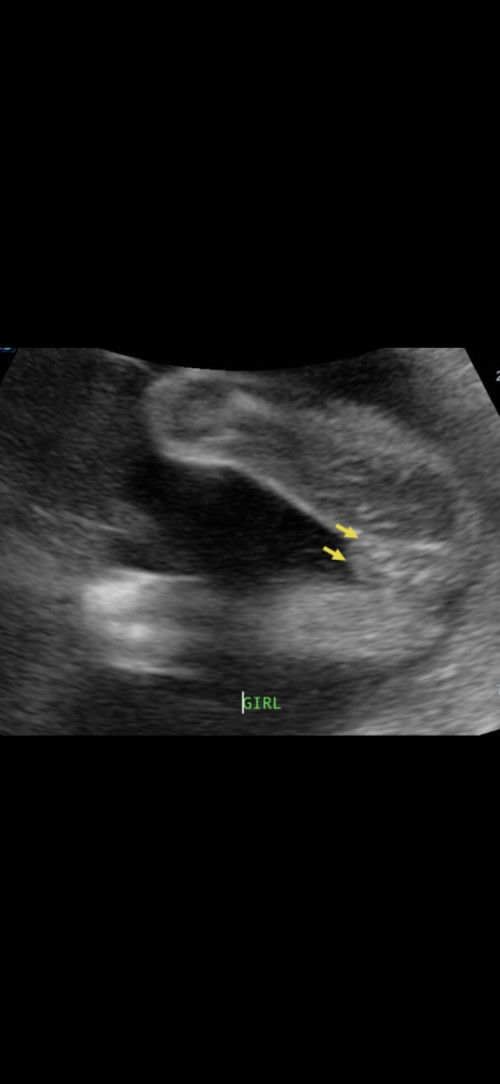

Scan baby tapi girl

ni girl. klu perati betul2 ada line kt tgh tu.